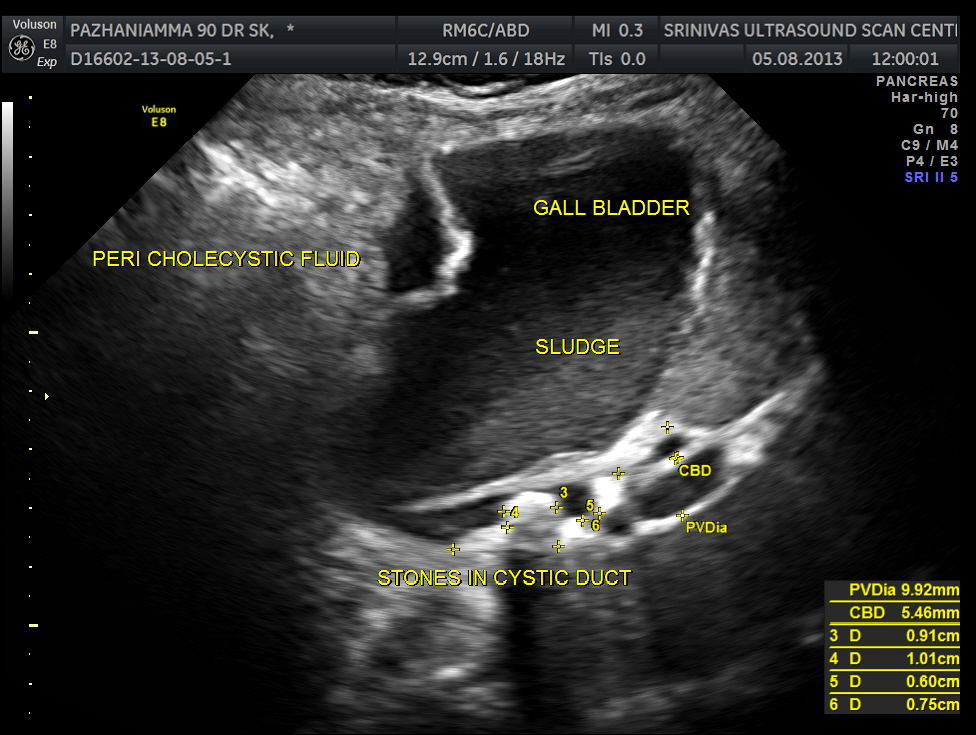

grossly distended gallbladder , with sludge and gallstones and fluid around the gall bladder.

SUB DIAPHRAGMATIC COLLECTION , PROBABLY LOCULATED WAS ALSO SEEN. MINIMAL RIGHT PLEURAL EFFUSION WAS ALSO SEEN.

The diagnosis was : acute calculous cholecystitis , cystic duct stones causing a rupture and fluid collection around the GB and loculated sub diaphragmatic collection with reactive mild right pleural effusion . Endometrial fluid collection needed further evaluation.